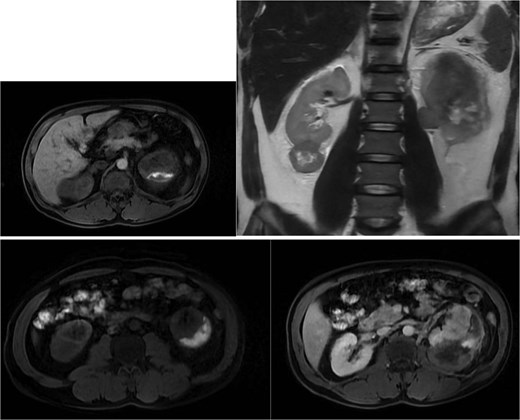

Abdominal magnetic resonance imaging (MRI) showed approximately seven to eight right renal masses (largest 32 × 35 × 37 mm) and five to six left renal masses (largest 62 × 55 × 55 mm). The renal lesions were iso- to mildly hypointense on T1-weighted imaging and mildly hypointense on T2-weighted imaging, without macroscopic fat. Post-gadolinium images demonstrated heterogeneous enhancement with central necrosis in the dominant masses (Fig. 3). Diffusion-weighted imaging showed marked restriction in the viable tumor components (Fig. 4). The dominant left renal mass, located in the mid kidney, demonstrated invasion of the posterior renal fascia. Subacute hemorrhage under the left renal capsule measured up to 24 mm in thickness.

Axial T1-weighted and T2-weighted MRI showing multiple solid renal masses with low signal intensity and a large left subcapsular hematoma.